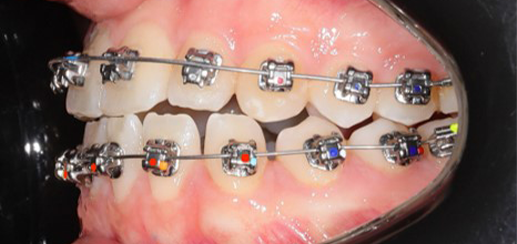

Initial leveling in the maxillary arch was carried out with a 0.014 CuNiTi archwire. This was followed by a 0.018 CuNiTi wire, with stoppers positioned mesial to the molars and activated to provide protrusion of incisors. The mandibular arch was then bonded and initial alignment was achieved with a 0.014 CuNiTi wire, then both jaws are progressing to 0.014 × 0.0275 CuNiTi and subsequently 0.018 × 0.0275 CuNiTi for torque control.

Finishing was completed with a 0.018 × 0.0275 TMA archwire in conjunction with Class III elastics.